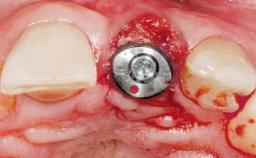

A 33-year-old female patient presented with an upper left central incisor that required extraction after a failed endodontic therapy. The tooth had been traumatized when the patient was a teenager and had undergone several endodontic treatments, including two apicectomy procedures. The patient was in good health and did not smoke. Clinical examination showed that the patient had a high lip line. In full smile, the gingival margins of the upper teeth were visible to the first molars. The gingival margins of central incisors 11 and 21 were only just showing. Examination of tooth 21 confirmed that the tooth was mobile and had hypererupted by 1 mm.

Placement Protocol Immediate implant placement

Tooth Site Maxillary incisor or canine

Socket Morphology Single-root socket

Socket Integrity Damage to one or more bone walls

Bone Volume Damage to one or more socket walls